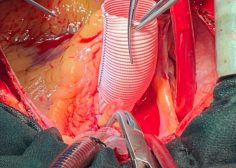

Innovative technique for sizing ascending aorta tubular graft during bentall operation

Innovative technique for sizing ascending aorta tubular graft during bentall operation.